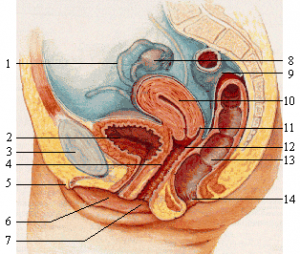

G – точката влезе в светлината на обективите през 2008 година, когато сексологът Емануеле Джанини от Италия доказа, че в тялото на всяка жена има изключително чувствителна точка, която ако бъде стимулирана правилно, ще докара дамата до върховен оргазъм. Това се дължало на струпване на нерви на едно място. Само две години след откритието на италианеца, в Англия пък патентоваха първата инжекция за оргазъм.